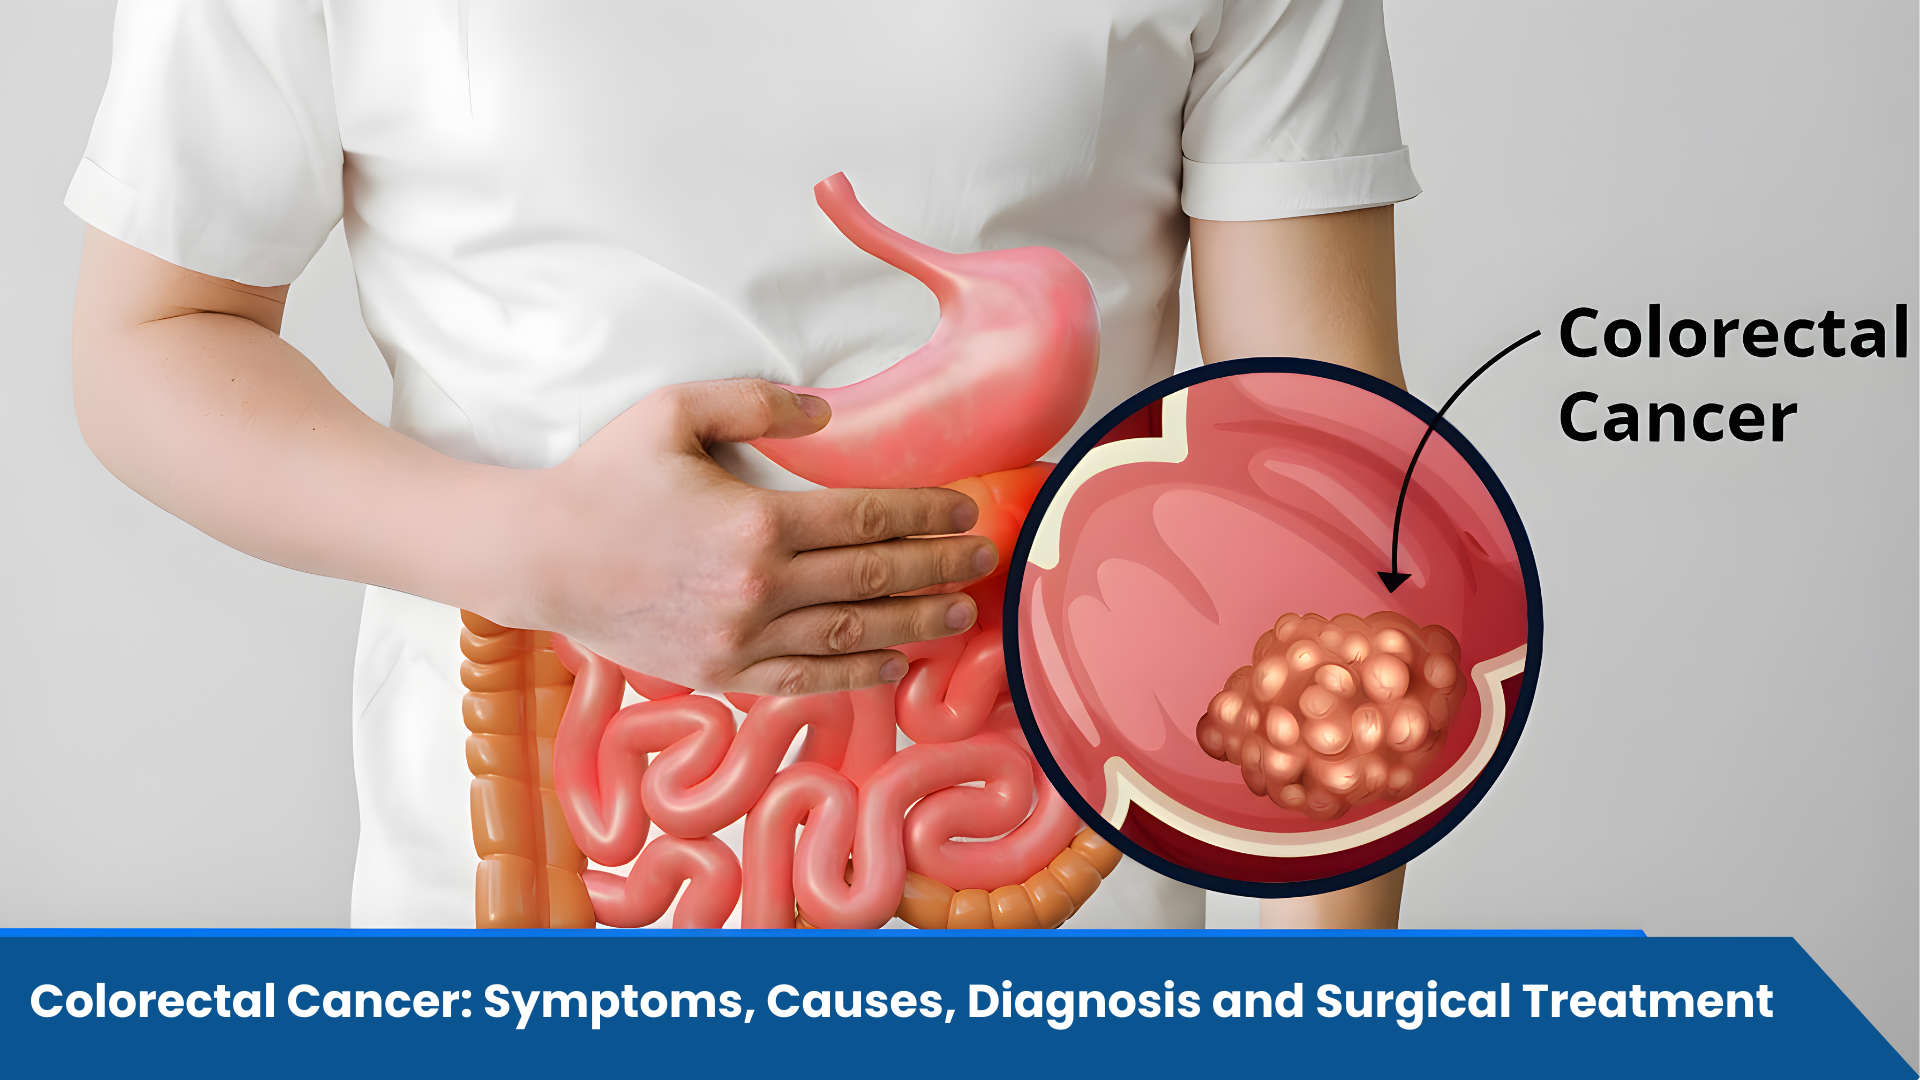

Best Colorectal Cancer Surgeon in Shalimar Bagh Delhi for Advanced Surgical Treatment Colorectal cancer is one of the most prevalent types of cancer that affect individuals across the world and is increasingly being detected in India as well. It occurs…